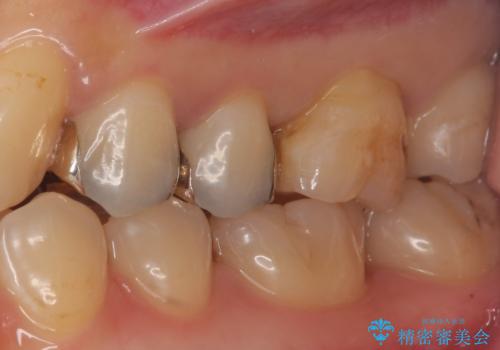

セラミックインレーによる治療

- 銀の詰め物を白くしたいとのことで来院。

銀の詰め物を除去した後、う蝕が残っていないかを拡大鏡下で確認し

セラミックの詰め物(e-maxインレー)にて治療を行いました。